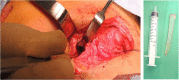

Case presentation: A nine year-old patient presented with a limited mouth opening (0.5 cm). Initial examination showed a scar of an old trauma in the submandibular area two months prior to presentation. The radiographic study showed a large knife-shaped foreign body with its tip at the infra-temporal region, and its base at the submandibular region. Further multi-slice computed tomography with angiography was done that showed close proximity of the foreign body to the branches of the external carotid artery; maxillary, lingual and facial branches. The foreign body was removed via extra-oral approach through the old scar of the past injury under general anesthesia. Dissection, exposure of the external carotid artery and preparing it for emergency ligation, were done before extraction of the foreign body. The patient's mouth opening increased to 2.5 cm without any complications.